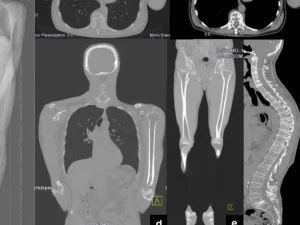

Tüm vücut MR, manyetik rezonans görüntüleme teknolojisi kullanılarak vücudun tamamının ayrıntılı bir şekilde taranmasıdır. Radyasyon içermeyen bu yöntem, manyetik alan ve radyo dalgaları yardımıyla organların ve dokuların yapısını detaylı bir şekilde gösterir. Doktorlar, bu görüntüleri kullanarak hastalıkları teşhis eder ve tedavi planlarını oluşturur.

Tüm vücut MR, genellikle hastalıkların erken teşhisi ve yayılımının değerlendirilmesi amacıyla çekilir. Özellikle kanser taramaları, inflamatuar hastalıklar, enfeksiyonlar ve dejeneratif hastalıkların tespitinde kullanılır. Ayrıca, vücutta mevcut olan anormalliklerin detaylı bir şekilde incelenmesi için de tercih edilir.

Tüm Vücut Emar için kullanılan MR Cihazlarımız en yeni teknolojiye sahip 3 Tesla özelliğine sahiptir. Tüm Vücut Emar yüksek çözünürlüklü ve çok net görüntüler doğru teşhis için son derece önemlidir. Tüm Vücut emar için anestezili seçenekler de mevcuttur.